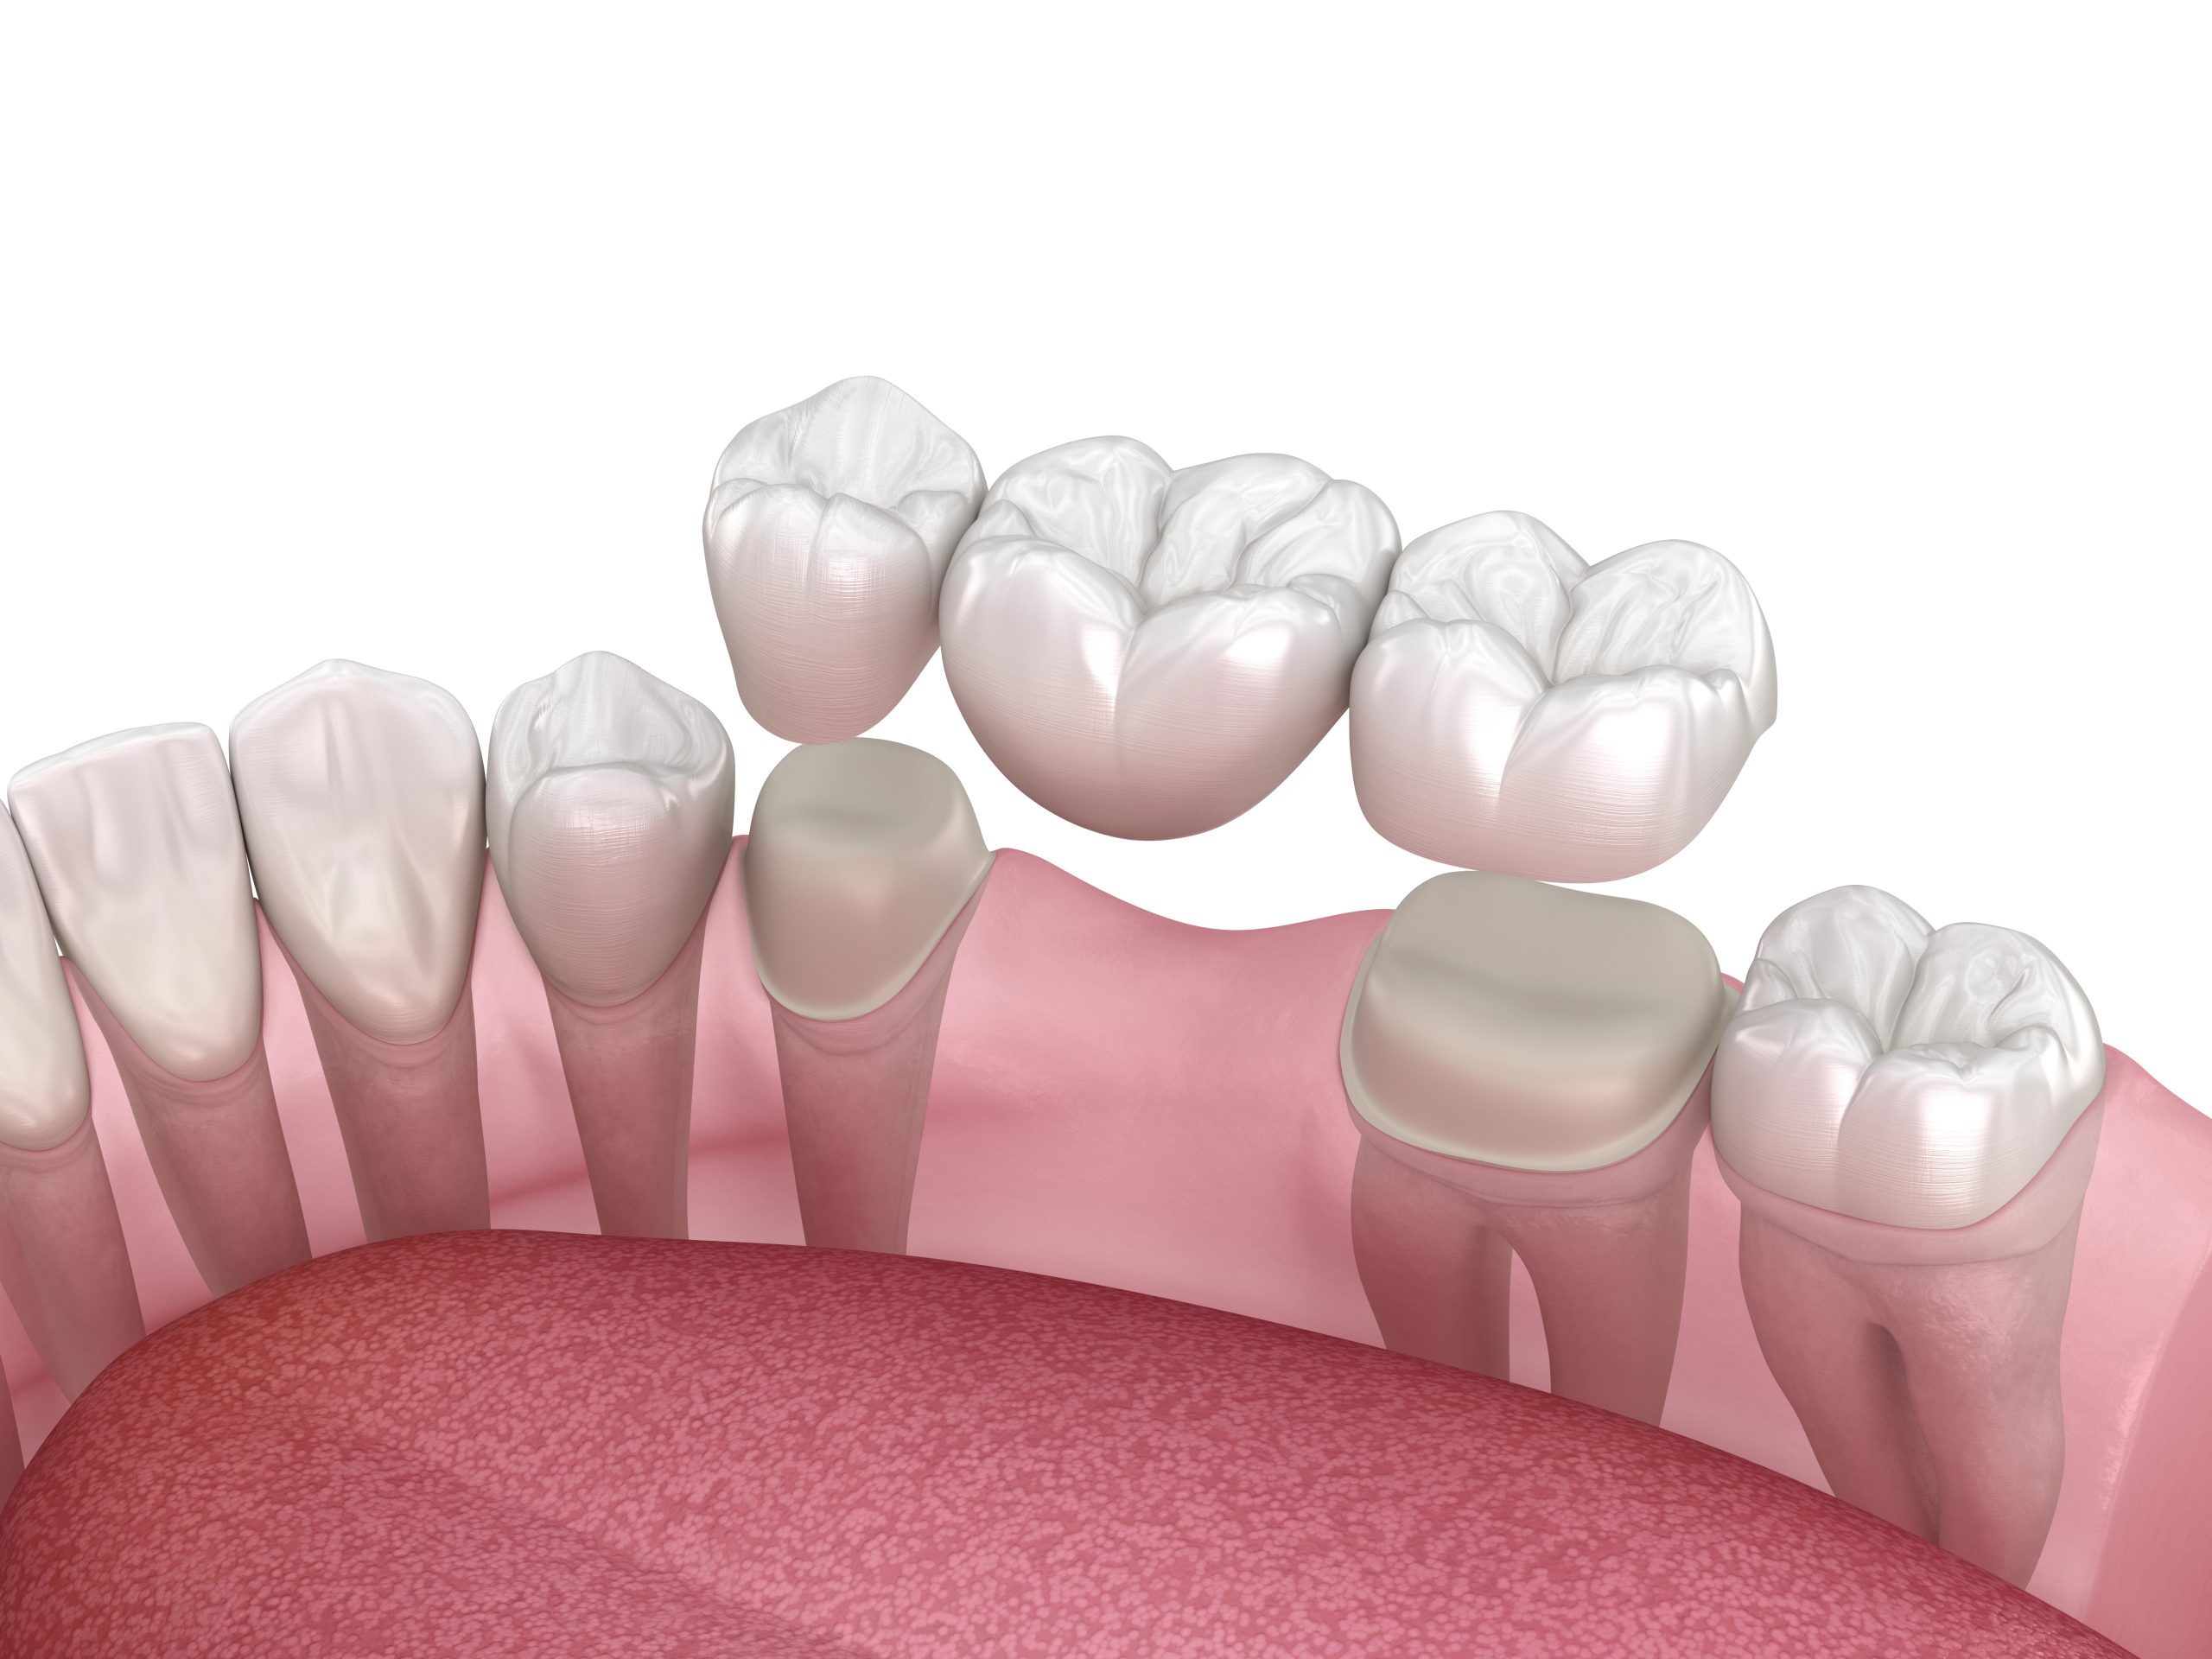

Dental Implants

PBM may help support healing after implant surgery by reducing inflammation and improving tissue recovery.